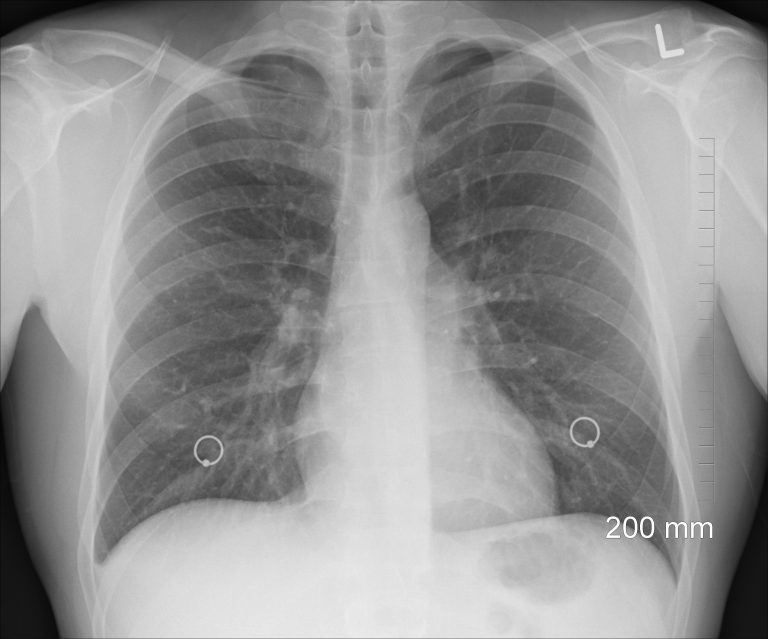

Chest Xray Cancer

Lung cancer CXR Radiology at St. Vincent's University Hospital Can A Chest Xray Show Early Lung Cancer if your doctor thinks there’s a chance that you have lung cancer or another lung problem, they will usually. research has not proven that vaping causes lung cancer. what you need to know. few patients with initial negative cxrs received a diagnosis of lung cancer within 6 weeks of initial cxr (n = 26/376, 6.9%). It. Can A Chest Xray Show Early Lung Cancer.

Lung metastases, portacath Radiology at St. Vincent's University Hospital Can A Chest Xray Show Early Lung Cancer few patients with initial negative cxrs received a diagnosis of lung cancer within 6 weeks of initial cxr (n = 26/376, 6.9%). research has not proven that vaping causes lung cancer. if your doctor thinks there’s a chance that you have lung cancer or another lung problem, they will usually. It can also help determine the type. Can A Chest Xray Show Early Lung Cancer.